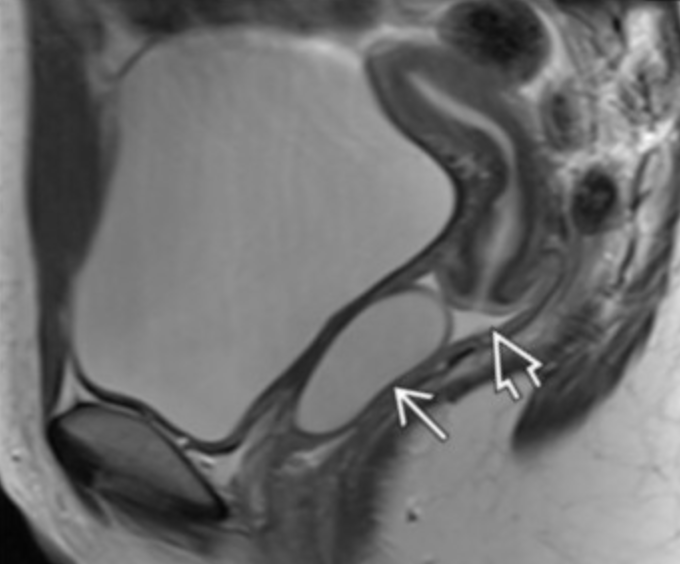

Junctional zone

• Arrow head = endometrium

• Middle arrow = junctional zone

• Long arrow = Outer myometrium